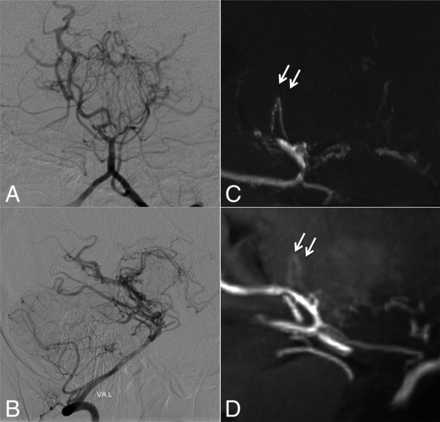

Case 6. Selective left vertebral angiography (anteroposterior, A; lateral view, B) shows no marked anastomosis. The MIP from TOF-MRA (C) demonstrates excellent visualization of inner thalamic anastomosis among posterior thalamostriate arteries (white arrows, type e), whereas the visualization is only moderate on MIP from MPRAGE (D).